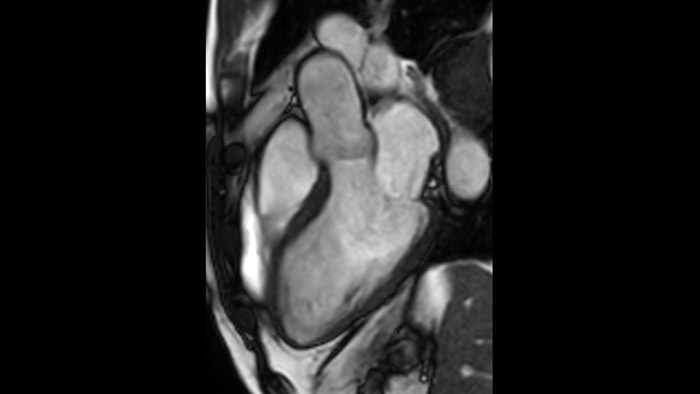

Comprehensive cardiac MR imaging

Diagnostic and prognostic utility of cardiac MR is increasing. Assess the anatomy and function of the heart using cine acquisitions, acquire information about perfusion and viability of the cardiac tissue, visualise potential edema with black blood sequence, access and even quantify tissue characterisation with CardiacQuant.